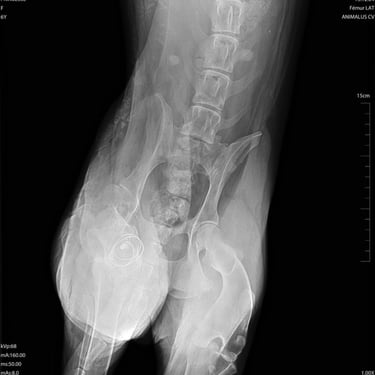

Nous voulions la prendre en charge après sa chirurgie, la mettre en pension et la préparer au départ pour qu'elle ait la chance de vivre quelques années heureuse dans une famille, mais la vie en a décidé autrement, malheureusement, et elle est décédée sur la table d'opération...